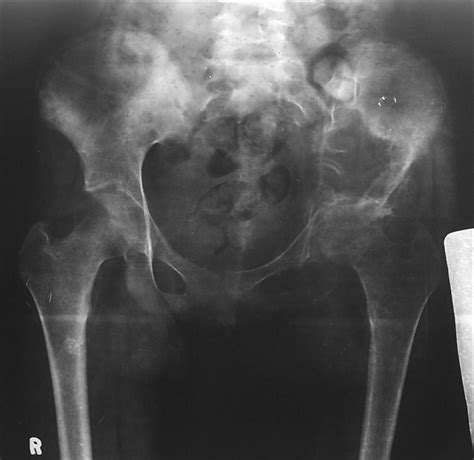

STOCK IMAGE, x-ray of the pelvis and lumbar spine frontal ... from www.medicalimages.com Bone pain is the most common warning sign of bone cancer, and it usually gets worse as tumor becomes larger. Stage 0 (zero) and stages i through iv (1 through 4). Bones commonly affected by secondary bone cancer include the spine, ribs, pelvis, and upper bones of the arms (humerus) and legs (femur). The stage provides a common way of describing the cancer t4: It can grow in any of the bones in the body. People with a fracture next to or through a bone tumor usually describe sudden severe pain in a bone that had been sore for a few months. Primary bone cancer is a rare type of cancer that begins in the bones. Pain may be worse at night, also becoming more constant.

Osteoplastic metastasis (prostate cancer) from www.klinikaikozpont.u-szeged.hu Although fever is rarely an early sign of bone cancer, it is a sign that the body is fighting an infection or illness. Because the cancer has spread, it is considered advanced or stage 4 cancer. The stage provides a common way of describing the cancer t4: Secondary cancer in the bone keeps the name of the original cancer. Women with ovarian cancer can experience back pain when fluid accumulates in the pelvis or when the tumor spreads in the abdomen or pelvis, directly irritating tissue in the lower back, says marleen. Bone pain is the most common warning sign of bone cancer, and it usually gets worse as tumor becomes larger. Bone cancer signs and symptoms. This spread of cancer is called a metastasis and can form a secondary cancer in another organ.